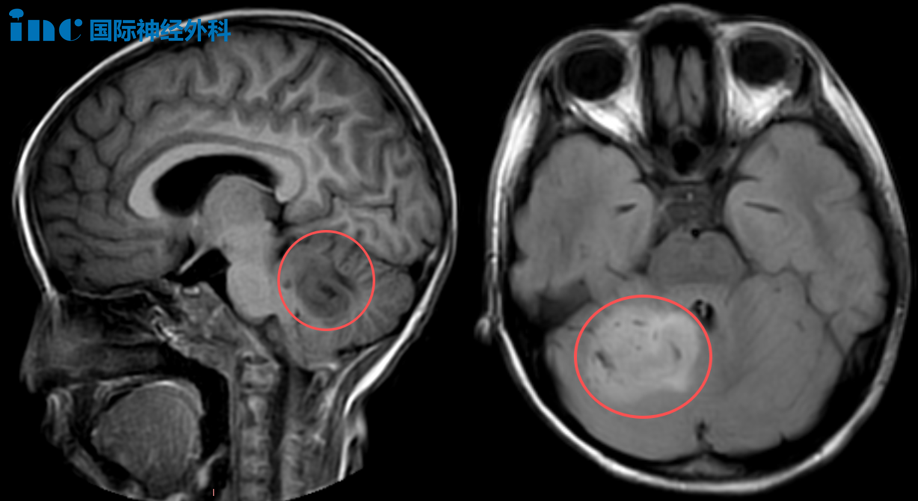

2025年9月15日,不到7岁的女孩乐乐在放学回家后,向父母抱怨起自己白天有些头晕疲乏。检查发现“小脑占位”,考虑低级别胶质瘤。尽管乐乐之后的状态有所好转,但由于病变体积较大,她仍不时头晕头痛、精神不振,总想睡觉。面对这一切,父母深知,必须尽快为孩子扫清前路上的障碍。

小脑半球堪称人体运动的"精密指挥官",掌管着同侧肢体的协调运作,确保每一个动作都精准、流畅且平衡。当这个重要区域受损时,患者就会出现典型的同侧肢体共济失调症状——动作变得笨拙不协调,出现意向性震颤,连最基本的站立行走都摇摇晃晃。此外,小脑缄默综合征(cerebellar mutism syndrome,CMS),又称后颅窝综合征,是小脑-脑干术后的常见并发症之一,发生于后颅窝肿瘤(如脑干、小脑、四脑室肿瘤)切除术后的患者,由于其特点以缄默症,即无法说话为主,因而又被称为“沉默的小脑”。

巴教授的评估为他们带来了希望的曙光,“积极一些来看,这大概率仅是低级别肿瘤。甚至可能是错构瘤。两个积极迹象是:孩子尚未出现严重临床症状,且周围未见明显水肿,因此判断这并非高级别肿瘤。手术对我来说并非难事,我能做到!”

“手术吧!”这个决定,乐乐父母做得果断而坚决。在今天的术前谈话中,巴教授再次向家长说明,孩子的肿瘤很有可能是错构瘤,如果是这样预后将会非常理想。